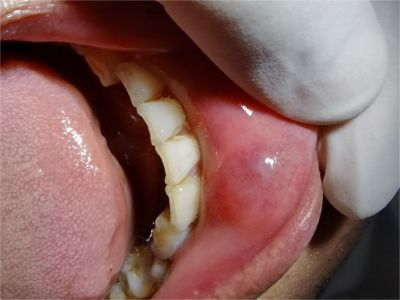

唇内侧

肉粒

外渗性黏液囊肿下嘴唇内侧有红色肉粒图

外渗性黏液囊肿会导致患者下面的嘴唇内侧出现一个球形的红色肉粒,有黄豆大小,边界清晰,表面平滑且有光泽,呈半透明状,囊肿容易被咬破,破裂愈合后可再次形成囊肿。